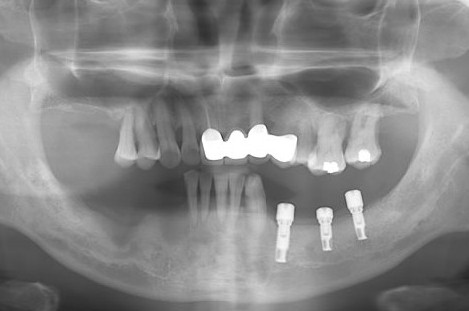

多顆種植牙成功的全景片

全景x片一般在拔智齒、以及正畸還有種植牙、嚴(yan) 重蛀牙的時候等都需要進行,可以看到智齒的位置,以及萌出方向,是否對鄰牙有危害;可以看到全口牙齒排列的基本情況,比如是否有牙齒擁擠不齊,咬合不好等;還可以看到口腔是否有缺失牙,以及是否有其他修複體(ti) ,是否有殘根需要拔除;還能檢查出是否有蛀牙,以及蛀牙的大致情況,可能需要進一步拍小牙片確定。